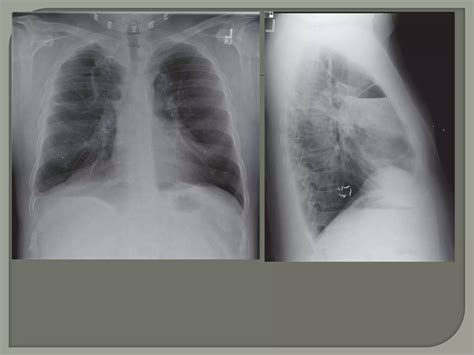

Medical professionals categorize the severity of the disease based on the size of the bullae and the impact they have on the patient’s respiratory function. The table below outlines how these bullae are typically classified in clinical practice.

Classification Bulla Size Clinical Impact

Small Bullae 1–5 cm Minimal symptoms; usually stable.

Large Bullae 5–10 cm Noticeable breathlessness; potential compression.

Giant Bullae > 10 cm Severe, requiring urgent evaluation and potential surgery.

⚠️ Note: Always consult with a pulmonologist to undergo diagnostic imaging, such as a CT scan, as chest X-rays may not always reveal the full extent of the bullae.

Diagnostic Procedures

Diagnosis begins with a thorough medical history and physical examination. However, imaging is essential to confirm Bullous Lung Disease. High-resolution Computed Tomography (HRCT) is considered the gold standard for visualizing bullae. It allows physicians to determine if the bullae are localized or widespread and whether they are compressing functional lung tissue. Pulmonary function tests (PFTs) are also conducted to measure lung capacity and identify the degree of airflow obstruction.